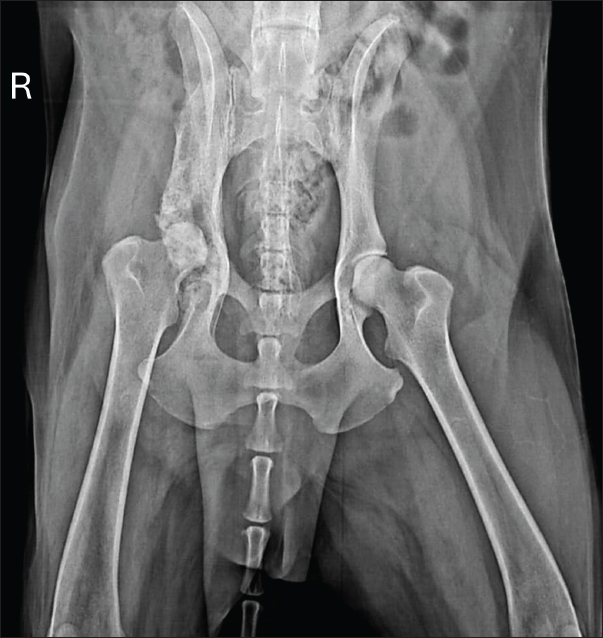

At 150 days, reevaluation included radiography and hematology, which remained within normal limits, including hepatic and renal parameters. Radiographs showed marked reduction of periosteal proliferation and osteolytic areas, primarily concentrated in the acetabular region, likely due to joint degeneration from the infection (Fig. 6).

Fig. 6. Radiographic examination of the dog 150 days after initiation of itraconazole treatment, showing marked reduction of periosteal proliferation and osteolytic areas.

The patient was reexamined 16 months (480 days) after treatment initiation. The owners reported the patient to be in good general condition, with normal appetite and no clinical alterations. Hematology remained normal. Radiographs revealed slight residual osteolysis, particularly in the acetabular region (Fig. 7). At the time of this report, the dog was on itraconazole and gabapentin with periodic renal and hepatic monitoring and has shown no progression or evidence of systemic aspergillosis.

Fig. 7. Radiographic examination of the dog 480 days after initiation of itraconazole treatment, showing a slight reduction in the osteolytic areas, particularly in the acetabular region.